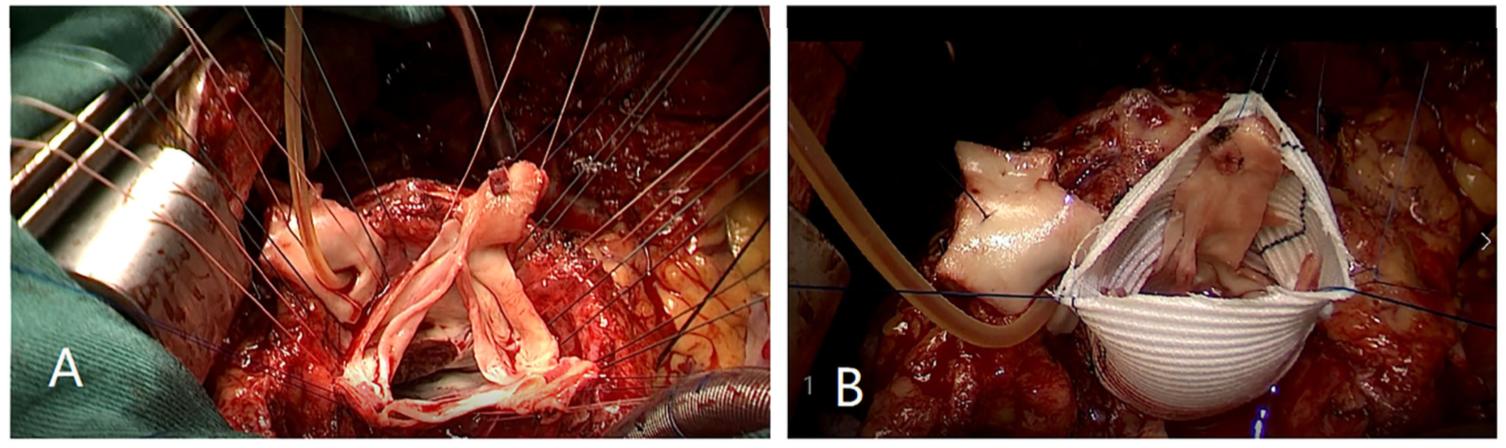

首先,通过右腹股沟切口完成股动脉和静脉的分离。然后进行胸骨正中切口,完成上下腔静脉的分离。随后,在稳定的股动脉和静脉以及上腔静脉插管后建立体外循环(CPB)。钳夹升主动脉,在34℃下启动组氨酸-色氨酸-酮戊二酸溶液(HTK)心脏停搏液。在窦房结上方1cm处横切主动脉。肉眼可见主动脉环扩张和窦扩大。主动脉瓣未增厚,瓣叶保存良好。然而,由于主动脉根部扩张,小叶与主动脉瓣环不匹配,这将导致主动脉瓣错位。评估主动脉瓣功能后,通过主动脉瓣在左心室流出道中看到增厚的肌束,并用鱼腹式刀片移除增厚的肌丛。然后,分离主动脉根部,测量三个瓣叶连合与瓣环之间的距离。同时计算了三个小叶的中点和根部之间的距离。切割主动脉瓣环上方3mm处的主动脉根部(图3A),并选择32mm人工移植物。合理调整小叶连合的高度,在近端吻合过程中,通过水平垫缝合将小叶的每个尖端固定在人工移植物内(图3B)。左冠状动脉和右冠状动脉的吻合通过按钮技术完成。最后,在主动脉和移植物之间进行远端吻合。在充分复温后,升主动脉断开,生理心律自动平稳激活。术中食管超声检查未发现明显AR。当血流动力学和生命体征稳定时,体外循环停止。在没有任何活动性出血的情况下,对左、右胸腔进行了调节性胸腔闭合和纵隔引流。

图3.(A)切割主动脉瓣环上方3mm处的主动脉根部。(B)在近端吻合过程中,通过水平垫缝合将每个瓣叶尖固定在人工移植物内。